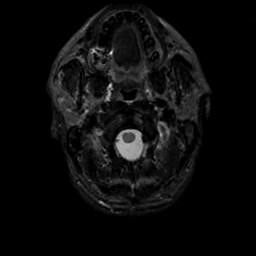

MR Study #13, May 19, 1991 -- Slice #1